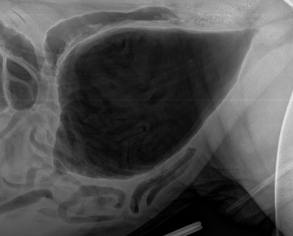

What is being shown on this radiograph?

Mineralised calculi opacities present within the bladder lumen

Urethra has been collimated out of the radiograph —> retake radiograph to see if mineralised calculi is along length of urethra